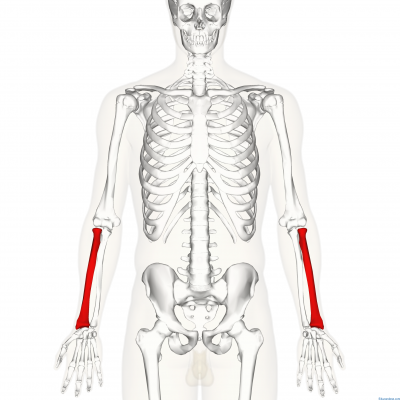

Hombro y codo Helico sales, Molestias en el hombro al empujar algo con la mano o brazo Dr Michell Ruiz Especialista en Hombro Codo Rodilla. Ciudad de Mexico. Hospital Angeles Metropolitano sales, RECONSTRUCCION ARTICULAR DE HOMBRO Y CODO OrtoClinica del Norte sales, Hombro y Codo Dr. Jose Luis Hernandez sales, Protecciones para codos y hombros nivel 2 conjunto de codos y hombros. Outlete.es sales, HOMBRO Y CODO Facebook sales, Ejercicios de hombro Traumatologia Hellin sales, Hombro y Codo Traumatologo Murcia Doctor Alonso Lison sales, HOMBRO Y CODO sales, Dolor en los hombros y codos Te digo varios ejercicios para prevenirlo tips sales, Fortalecimiento de hombros y codos sales, ANATOMIA Y FISIOLOGIA DEL SISTEMA OSEO sales, Unidad de hombro y codo Archivos Clinica DKF sales, Manejo del dolor de hombro y codo sales, HOMBRO Y CODO sales, Dr. Marlon Zeledon Ortopeda Cirugias de Codos Hombros sales, Traumatologo patologia hombro y codo Madrid Clinica MipSalud sales, Giro de hombros Codos doblados Yoga de cerca Skandha Chakra Secuencias de Yoga Beneficios Variaciones y Pronunciacion en Sanscrito Tummee sales, ORTOPEDIA HOMBRO Y CODO TRAUMATOLOGIA DR. CARLOS E. CAMPOS sales, Traumatologo para lesiones de hombro y codo en Almeria Claudio Vazquez Colomo sales, Onura Gunea SUFRES DOLOR EN TU HOMBRO O CODO IMPORTANCIA de la Estabilidad Escapular Omoplato La cintura escapular requiere de un gran trabajo de Movilidad Estabilidad y Fuerza. Y tras un sales, Hombro codo y muneca PPT sales, El Hueso entre el Hombro y el Codo y sus funciones Cirugia de hombro sales, Text Cuando su hijo tiene codo del lanzador u hombro del lanzador sales, El Hueso entre el Hombro y el Codo y sus funciones Cirugia de hombro sales, Traumatologia y Unidad de Hombro y Codo en Madrid Clinica DKF sales, Traumatologo patologia hombro y codo Madrid Clinica MipSalud sales, Terapia de mano hombro codo Academia de terapia de manos sales, Dolor en el Hombro Tipos de Dolor Causas y Tratamientos Dr Michell Ruiz Especialista en Hombro Codo Rodilla. Ciudad de Mexico. Hospital Angeles Metropolitano sales, Lo que debes saber sobre las lesiones en hombros y codos Hospital Internacional de Colombia sales, Dolor de hombro codo muneca y tratamiento OptiMMus sales, Lo que debes saber sobre las lesiones en hombros y codos Hospital Internacional de Colombia sales, Hombro y codo 1001813 VR3170L Sistema Esqueletico 3B Scientific sales, Hombro y Codo Clinica Ciudad del Mar sales, Lo que debes saber sobre las lesiones en hombros y codos Hospital Internacional de Colombia sales, Product Info: Hombros y codos sales.